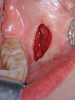

Fig 4.. Minimally invasive orthognathic surgery, intraoperative views of incisions in the maxilla (Fig 4), mandible (Fig 5), and chin (Fig 6).

Figure 4